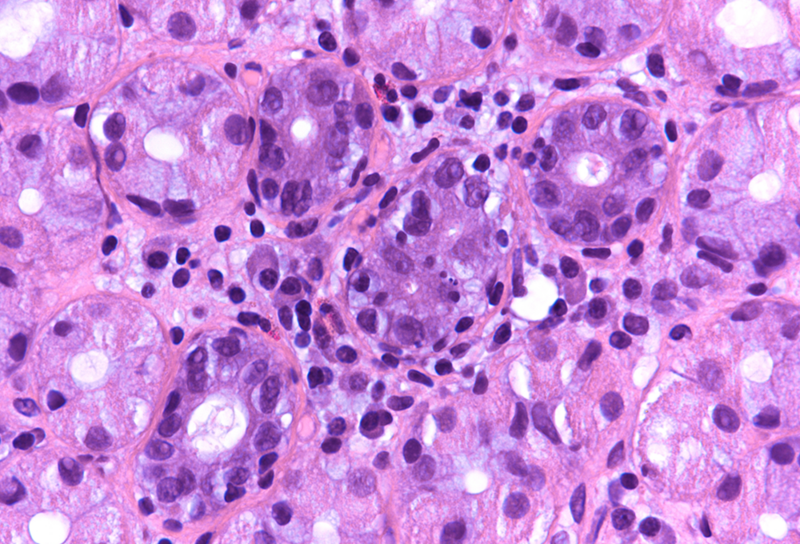

Microscopic examination revealed superficial chronic-active antrum and corpus gastritis (Panel A). In the mucus layer close to the surface epithelium, comma-shaped bacterial structures were detected and highlighted with a Warthin-Starry stain, consistent with Helicobacter pylori (Panel B). In the biopsies obtained from the corpus mucosa, a multifocal, predominantly lymphoplasmacytic infiltrate was seen in deeper parts of the mucosa. Specifically, the oxyntic glands were surrounded and infiltrated by lymphocytes (“emperipolesis”) resulting in gland destruction and parietal cell apoptosis. Occasional eosinophils completed the picture (Panels C-E). No significant atrophy and no metaplastic changes were observed.